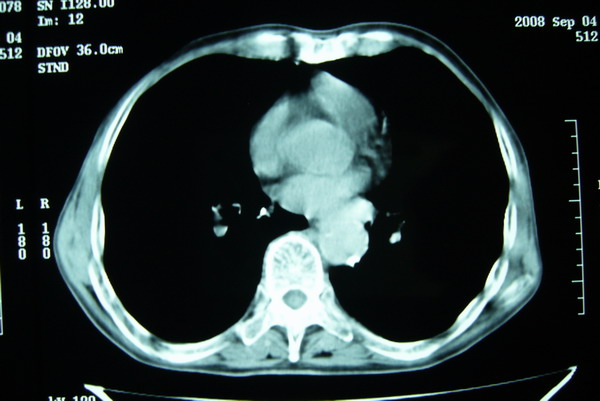

标题: CT15579:男 86岁 咳嗽 咳少量白痰 发热2天 吸烟史60年 [打印本页]

标题: CT15579:男 86岁 咳嗽 咳少量白痰 发热2天 吸烟史60年

右上周围型肺癌,慢支,肺气肿。

分叶及少量边缘性钙化,老年人,周围性肺癌首先考虑。

右肺上叶巨大软组织肿块,轮廓不规则,纵隔内有肿大淋巴结,首先考虑肺癌。

右上肺一不规则团块,边缘有分叶和毛刺,纵隔有淋巴结肿大。右肺周围性肺癌首先考虑。